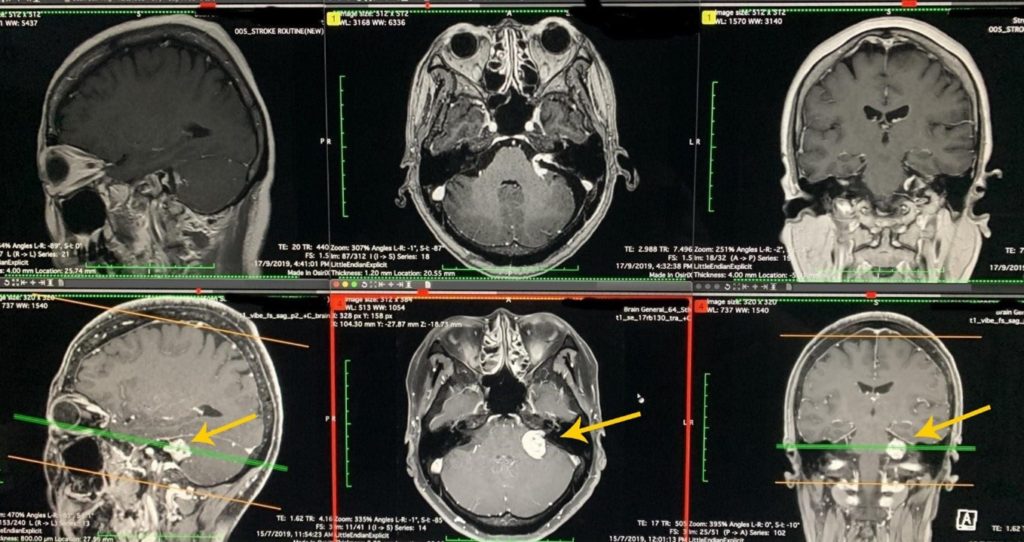

磁力共振影像診斷

磁力共振醫學影像檢查,有助於明確診斷及鑑別小腦腦橋角區域的腫瘤,例如腦膜瘤、表皮樣囊腫、三叉神經鞘瘤等的鑑別。

聽覺神經瘤的磁力共振影像特點:

腫瘤對小腦、腦幹的壓力。

可見聽覺神經瘤由內聽道向內側長出來,像蝌蚪的尾巴一樣。

下排MRI: 手術前影像; 上排MRI:保存聽力的腫瘤減壓手術後影像